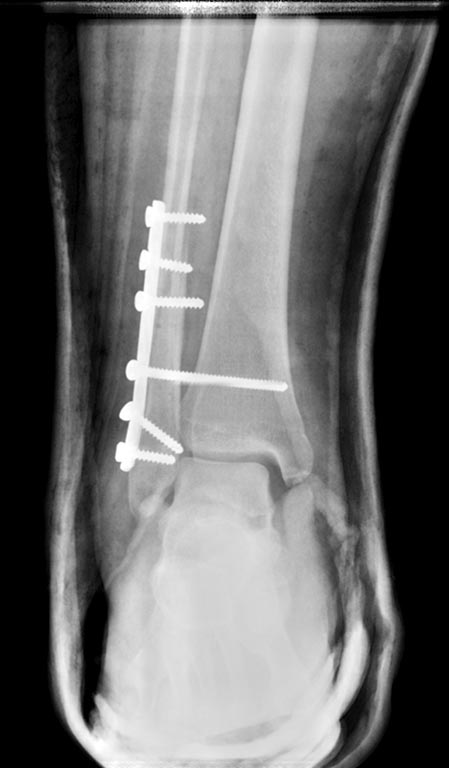

Перелом наружной лодыжки с разрывом ДМС и дельтовидной связки и подвывихом стопы. Пациенту 17 лет, полного телосложения. На контроле сохраняется небольшой подвывих стопы.

Шов дельтовидной связки не выполнялся. Так оставлять или реостеосинтез? Интересует дальнейшая тактика. Смущает молодой возраст пациента...

Пластина короткая (учитывая то, что перелом заканчивается на уровне 2 винта сверху), надо было минимум на 3-4 отверстия брать длиннее. Винт, фиксирующий синдесмоз похоже пошел на изгиб. Может сломаться, как мне кажется. Второй снизу винт - сделайте рентгенографию с ротацией, складывается ощущение, что он в суставе. И да, "вилка" расширена. Я бы взял губчатый шнековый винт, стопу в 90 градусов при сверлении, при закручивании винта чуть сжимаю кости выше введения винта.

подвывих сохраняется за счет того, что недорепонировали малоберцовую кость и синтезировали ее с укорочением. Хотелось бы увидеть боковую и Mortise проекции, узнать о сроках с момента травмы и операции .

У всех с железом одно и то же, НО, длина пластины сдесь не играла критичной роли. Линия перелома длинна, косая, можно отрепонировать, стягивающие винты, а Вашу пластину затем как нейтрализующую. Лодыжка " не дотянута" отсюда и подвывих. Если быть педантом, то реостеосинтез. Хотя, видел и хуже с неплохим отдаленным результатом.

Даниил 03 Октябрь 2015, 00:44

Проведите реостеосинтез: удалите пластину, отрепонируйте малоберцовую кость, восстановив ее длину, проведите межфрагментарную компрессию стягивающим винтом, а затем установите нейтрализующую пластину. Можно и старую пластинку положить, если ее установить по задней поверхности малоберцовой кости (тогда стягивающий винт проводите через одно из отверстий пластины). Ну и для фиксации ДМБС 3,5 мм винт.

А вы посмотрите на картинку внимательнее с увеличением. Дистальный фрагмент смещен под углом и, возможно по длине. отсюда и пляшем.

Согласен с коллегами, увидевшими проблему в недорепонированности наружной лодыжки. Сохранение укорочения в 1-2 мм может препятствовать правильному попаданию малоберцовой кости в вырезку. Трудно что-либо точно оценивать по имеющимся Rg-граммам: лучше сделать их без гипсовой повязки и обязательно AP-проекцию здорового голеностопного сустава. Я сделал бы реостеосинтез.

Здесь 3 проблемы:

1. Нет репозиции, диастаз сохраняется, возможно будут проблемы со сращением.

2. Дистальный винт в суставе, проксимальный винт в переломе на аксиальной проекции, синтез нестабильный, проксимальнее перелома даже 4 кортикалов фиксации нет.

3. Позиционный винт скользнул по большеберцовой кости, он не фиксирует синдесмоз.

Коль соблюдается техника АО (3 кортикала), может винт чуть покороче нужно было брать для маневра.

Также опираясь на рекомендации АО, ревизию дельтовидной нужно проводить при сохраняющемся подвывихе после фиксации позиционным винтом (правильной фиксации). По умолчанию ревизия дельтовидной связки не предусмотрена.

Минимально ИМХО что можно сделать под в/в: перепроведение позиционного винта, замена дистального винта и гипс в варусе...

По-хорошему это реостеосинтез.